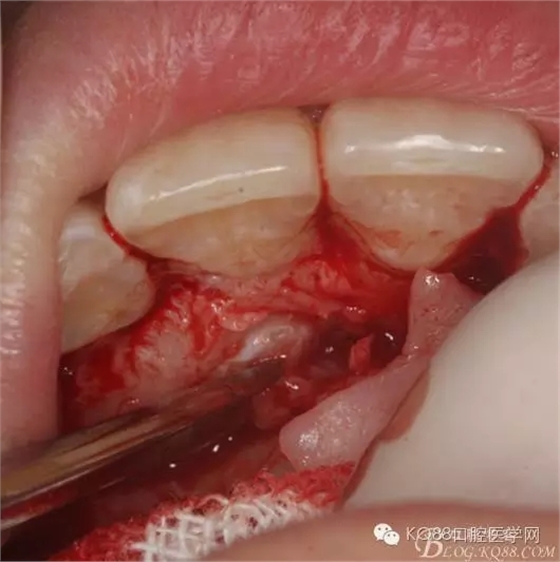

圖7.高速渦輪機(jī)去骨

圖7暴露埋伏的13牙冠

圖8.高速牙鉆橫斷13牙冠。比哦那個用牙挺分別挺出牙冠和牙根